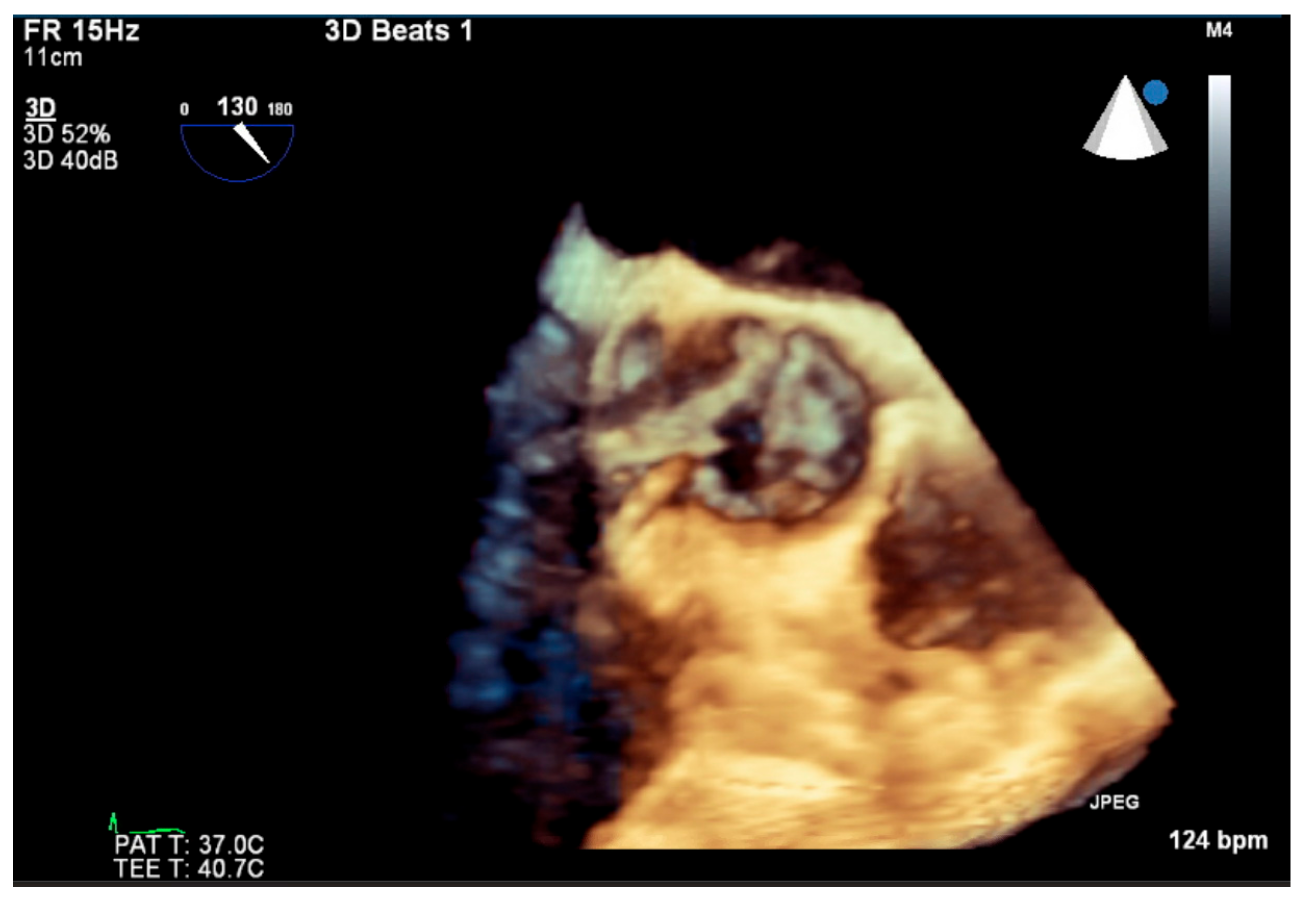

4. Investigations